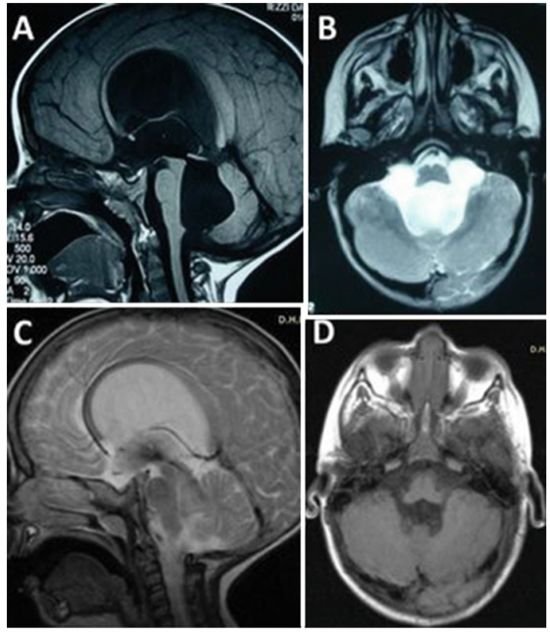

Concezio Di Rocco教授作为世界神经外科联合会基金小儿脑积水项目负责人,在脑积水手术方面经验丰富。在一份报告中,教授为一名因第四脑室出口狭窄导致脑积水,合并小脑功能异常共济失调的3岁大的小男孩进行内镜下第三脑室造瘘术,成功控制了脑积水的产生,手术过后小男孩症状迅速消退,预后效果非常好。